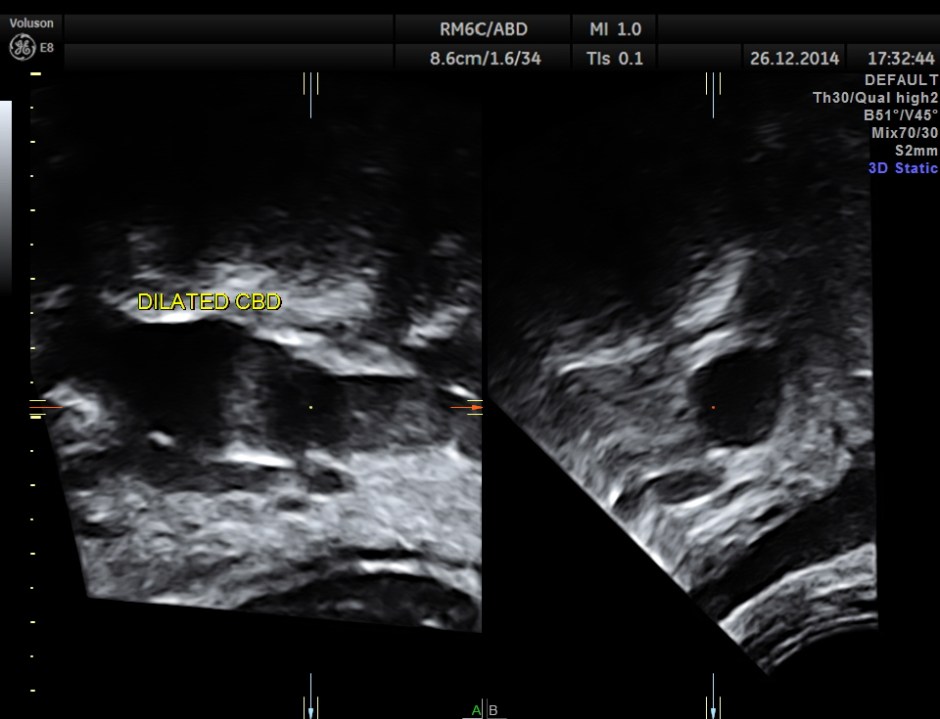

grossly dilated common bile duct.

3 d reconstruction of extra hepatic CBD